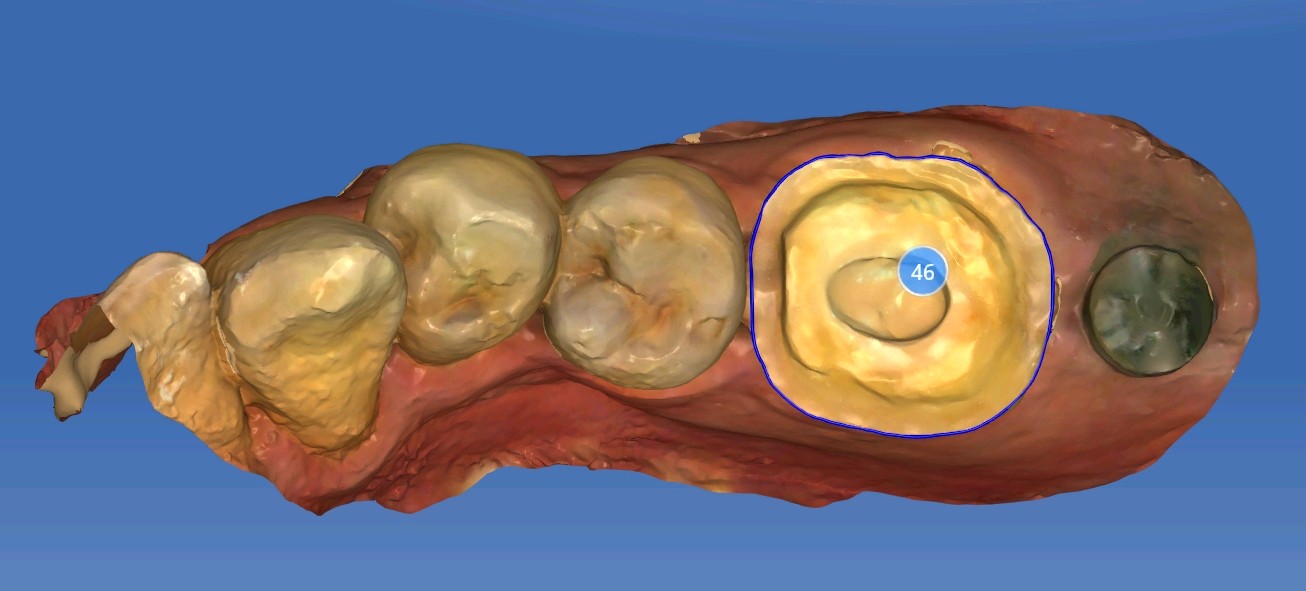

术后

补牙在操作过程中很容易受到唾液污染、口腔空间较小等因素影响粘结效果,长期磨耗容易脱落缺损。从而进一步引发继发龋。基牙很容易受损。根管治疗后的牙齿可以选择高嵌体和牙冠修复。这位患者牙体缺损不是较少,所以建议高嵌体修复。先用数字化口扫技术扫描患者口腔内备好的牙体形态,在口外模型上由专业技师制作出来,最后再由医生将嵌体粘固在缺损的牙齿上修复,因此治疗过程一般需要1-2次。更精细,密合度高,修复后牙缝不易塞牙 更好恢复咀嚼功能,窝沟点隙也更加清晰。